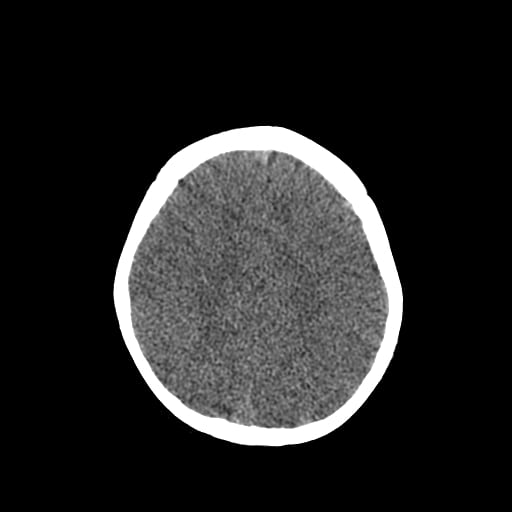

Age: 1

Sex: Male

Indication: Fall